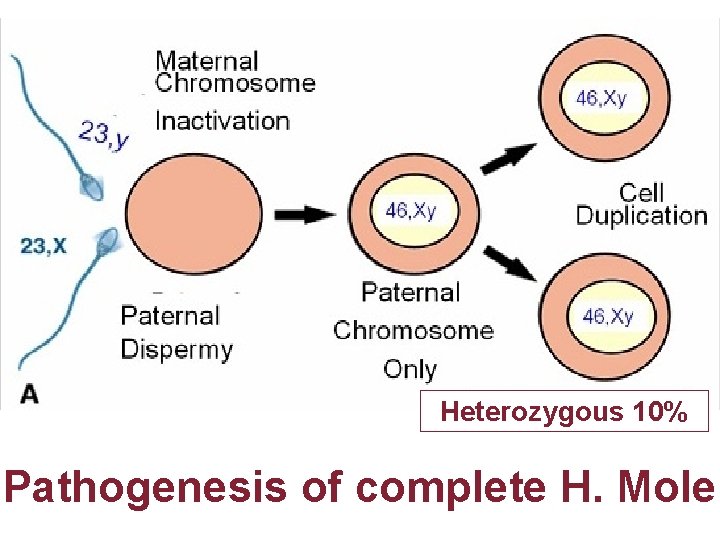

Karyotype

Heterozygous 10% Pathogenesis of complete H. Mole